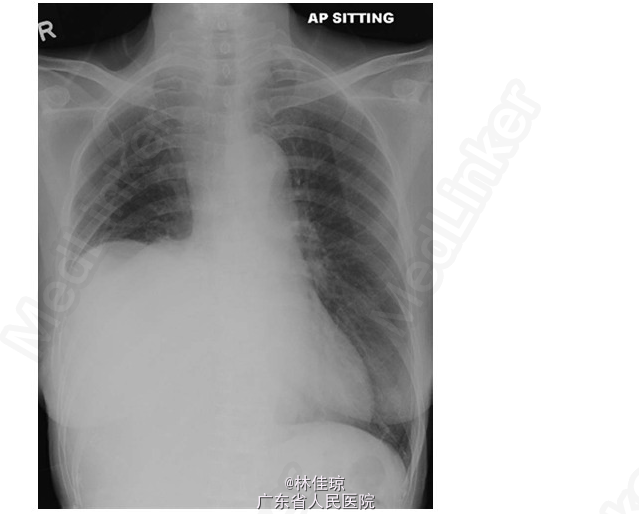

查体:生命体征正常,甲状腺肿大,中等大小,质地柔软,胸壁和右臂静脉扩张,无杵状指或发绀。第三肋下肺叩诊呈浊音,右胸下半部分呼吸音减弱;气管无偏斜。心腹查体均未见明显异常。 辅查: 末梢血血糖值为 1.9mmol/L。 血常规、生化、甲功均正常; 胸部 X 线片:显示胸部右下区占位性病变,密度均匀,界限清晰,右侧膈肌明显升高并可能膨出。 CT 扫描:胸部右下方有一巨大肿块,病变不均匀强化,大小 11.6×16.3×15.6cm;临近肋骨无破坏,但是临近肺、上下腔静脉受影响,证明为巨大胸膜纤维瘤。 组织病理学检查:对肿块进行 CT 引导下肺穿刺活检和组织学检查,可见梭形肿瘤细胞;有丝分裂像少见;梭形细胞 CD34 和 bcl-2 阳性,AE1/3 和 S-100 阴性。这些特征与孤立性纤维性肿瘤(SFT)一致。